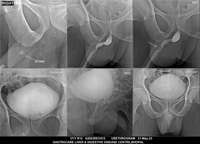

Section: URETHROGRAM

Total: 95 Cases